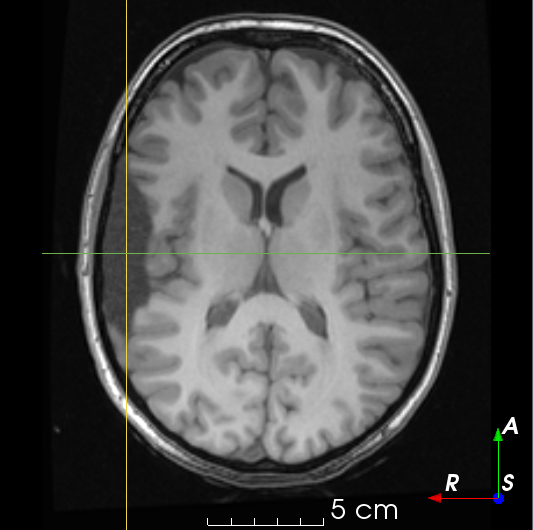

Refer to caption

(a)

(b)

(c)

(d)

(e)

(f)

(g)

(h)

Figure 6: Examples of challenging images for cavity segmentation. (a) Small frontal lesionectomy surrounded by hypointense white matter (b) Brain shift after contralateral temporal lobectomy (not shown) (c) Small frontal lesionectomy near the Sylvian fissure (d) Lack of boundaries between oedema and resection cavity (e) Possible blood clot within the cavity (f) Brain shift, oedema and resection cavity (g) Arachnoid cyst and resection cavity (h) Cerebellar degeneration. Green annotations represent areas that correspond to resection cavities; red annotations represent areas that do not.

Predictions errors are mostly due to 1) resection of size comparable to sulci (Fig. 6a), 2) unanticipated intensities, such as those caused by the presence of blood clots in the cavity (Fig. 6b), 3) brain shift (Fig. 6c) and 4) white matter hypointensities (Fig. 6e). Further work will involve using different internal and external cavity textures, carefully sampling the resection volume, simulating brain shift using biomechanical models, and quantifying epistemic and aleatoric segmentation uncertainty to better assess model performance [24].